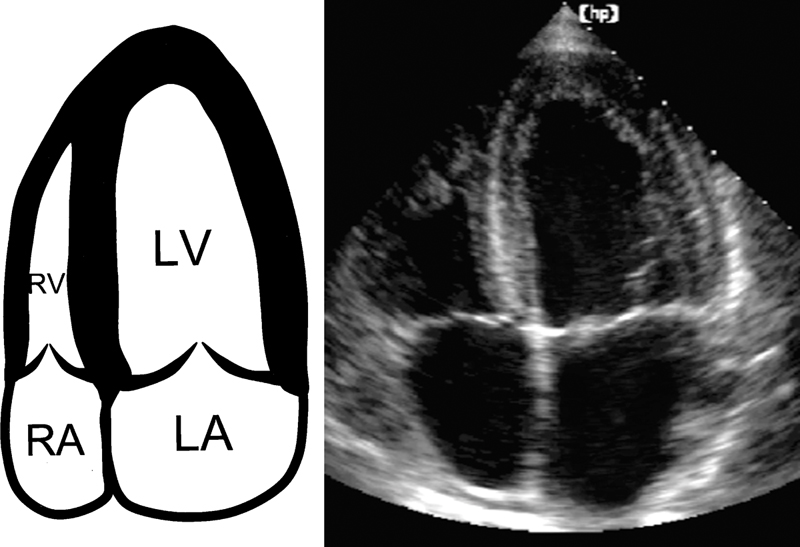

فحوصات تشخيصية لبعض امراض القلب والشرايين التاجية